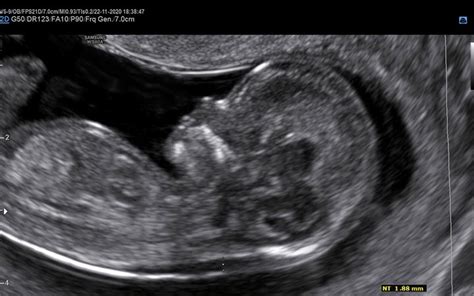

Ultrazvočno merjenje nuhalne svetline je časovno zelo specifično. Opraviti ga je treba med 11. tednom nosečnosti (ko je dolžina ploda od vrha glavice do trtice, t.h. rastne dolžine ali CRL, približno 45 mm) in 13. tednom nosečnosti ter 6 dnevi (ko je dolžina ploda približno 84 mm). V tem obdobju je meritev najbolj zanesljiva. Izven tega časovnega okvira lahko natančnost meritve upade.

Pregled nuhalne svetline se praviloma opravlja preko trebuha nosečnice, kar strokovno imenujemo transabdominalni ultrazvok. Le v redkih primerih, na primer ob neugodnem položaju ploda ali ob povečani telesni masi nosečnice, ko je vidljivost slabša, je lahko potreben pregled skozi nožnico - transvaginalni ultrazvok. Pred pregledom je nosečnico običajno prosijo, da popolnoma izprazni sečni mehur, saj to omogoča boljšo vizualizacijo ploda in natančnejše meritve.

Da bi zagotovili natančno merjenje nuhalne svetline, je ključnega pomena, da je plod v ugodni legi za merjenje. Zaradi tega lahko sam pregled traja različno dolgo, odvisno od sodelovanja ploda. Med samim ultrazvočnim pregledom strokovnjak opravi več pomembnih meritev in ocen: